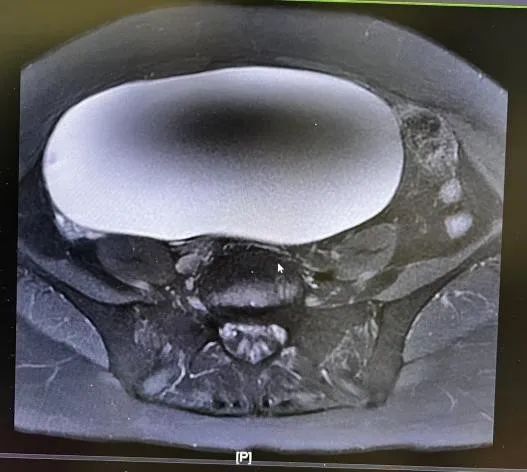

患者万女士因身体不适,在外院进行了检查后,结果发现盆腹腔有一个直径达20厘米的巨大囊肿。面对这一突如其来的疾病,万女士心情焦虑,急需找到专业的医疗机构进行治疗。在朋友的推荐下,她来到赣北医院妇产科就诊。

我院妇产科在收治万女士后,高度重视她的病情。为了更准确地了解囊肿的情况,科室迅速组织相关科室进行联合会诊。经过一系列细致入微的检查,妇产科团队对万女士的病情进行了全面且细致的术前评估后,得出了专业判断:该囊肿虽体积较大,但依据当前的临床表现、影像学特征及检验结果,诊断为良性囊肿。